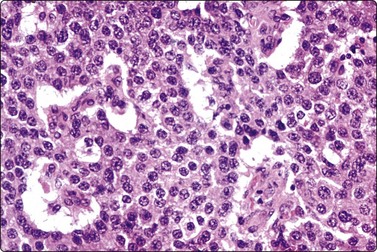

Rarest of all exocrine tumors of the pancreas is the highly aggressive acinar cell adenocarcinoma.107-112 The few cytologic case reports describe and illustrate highly cellular smears, with the cells in loosely cohesive aggregates, sometimes showing acinar formations. The cells having poorly defined granular cytoplasm, large smooth central nuclei, irregularly clumped chromatin, prominent chromatin clearing and large cherry-red nucleoli (Fig. 11.17).107,110,111 Distinction from islet cell tumor, which can be a problem, is generally made using immunocytochemical staining for exocrine enzymes and neuroendocrine markers, respectively.113 Zymogen granules are demonstrable, as are microvilli on ultrastructural examination.107,110,112

image

Fig. 11.17 Acinar cell adenocarcinoma

Loosely cohesive sheet of large, mildly pleomorphic cells with poorly defined granular cytoplasm, large nuclei with smooth nuclear membranes and prominent nucleoli (H&E, HP).